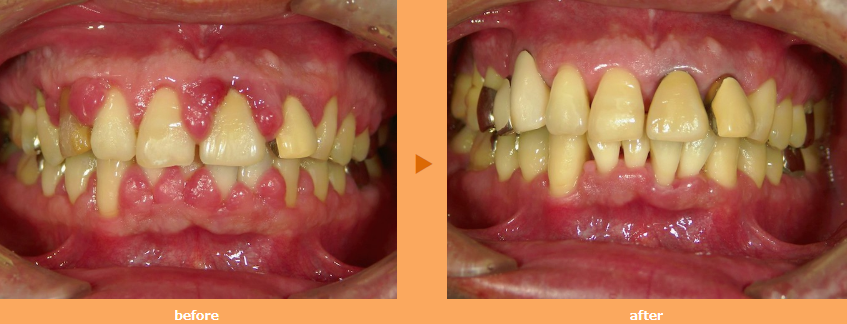

歯周病:歯を失う原因第一位です

歯周病は、歯茎や歯を支える骨が溶けてしまい、最終的に歯を失うという恐ろしい疾患です。40代以降のほとんどがかかっているといわれる歯周病は、歯を失う原因の第一位となっており、言わば国民病です。

歯周病の原因は、細菌のかたまり「プラーク」です。プラークは食後数時間で形成され、歯の表面に付着します。プラークは、酸素のない場所を好むので、歯と歯茎のあいだ(歯周ポケット)に潜りこみ、時間と共に増殖していきます。このプラーク中の細菌が出す毒素によって、歯茎に炎症が起き、歯周組織が破壊されてしまいます。

歯周病の怖いところは、初期の段階では、ほとんど自覚症状がないことです。口の中がネバネバしたり、歯茎の赤味があっても、痛みなどの症状はないため、見過ごされがちです。中等度の歯周病になると、骨が溶け歯がグラグラするといった症状があらわれ、硬いものが噛めないといった状態になります。

歯周病は、放っておくと歯を失ってしまうとてもおそろしい病気ですが、予防することは可能です。予防の基本は、日常の歯磨きをしっかりと行い、プラークを除去することです。プラークは歯と歯茎のあいだなどに付着していることが多いので、意識して歯磨きを行いましょう。

また、落としきれなかったプラークは、石灰化し硬い歯石になり、歯磨きだけでは落とすことができなくなってしまいます。歯石は歯科医院のクリーニングを定期的に受けることで落とすことができます。

大切な歯で一生快適に過ごすために、歯周病予防に努めましょう。